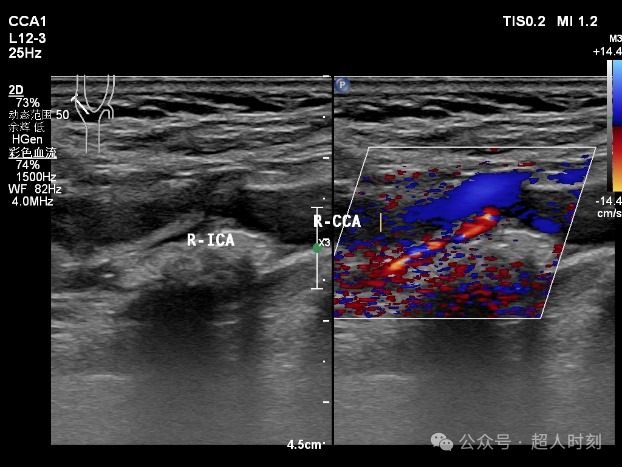

患者,男性,78岁,因“反复头痛头晕‚伴右眼黑朦1+年,肢体麻木偶感上肢无力6+月”入院。颈动脉彩超:右颈内动脉明显狭窄(狭窄率70%-99%),双侧颈总动脉多处狭窄(狭窄率<50%)。TCCD:颅内多支动脉狭窄(见图5)。

图5a 右颈内动脉颈段粥样斑块伴狭窄